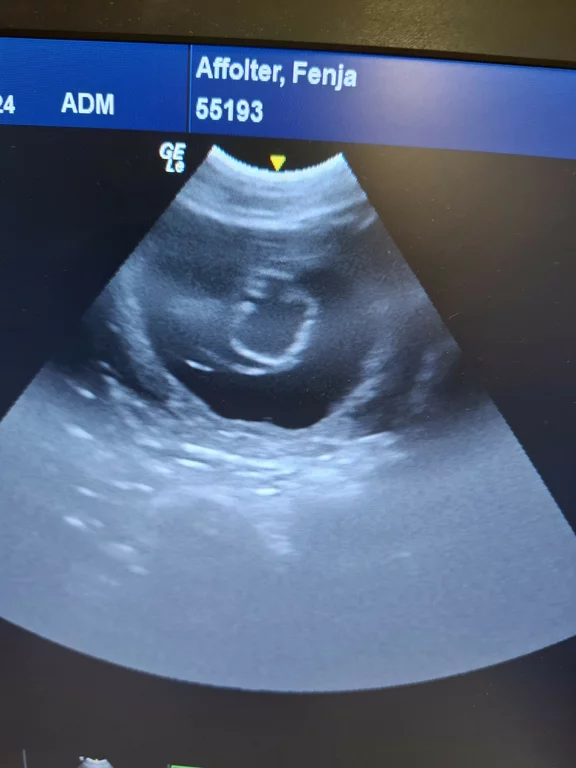

16.9.25 Tag 28 – Ultraschall

Heute waren wir beim Ultraschall und haben die wunderbare

Bestätigung erhalten: unsere Hündin ist trächtig! 💕 In der

Gebärmutter sind bereits kleine Fruchtanlagen sichtbar.

Zu diesem Zeitpunkt entwickeln sich die Embryonen weiter zu Föten – Augen und Ohren beginnen sich auszubilden, und auch die winzigen Pfoten mit ihren Zehenanlagen entstehen jetzt. Noch sind die Kleinen ganz zart, aber die wichtigsten Grundlagen für ihr weiteres Wachstum sind bereits gelegt.